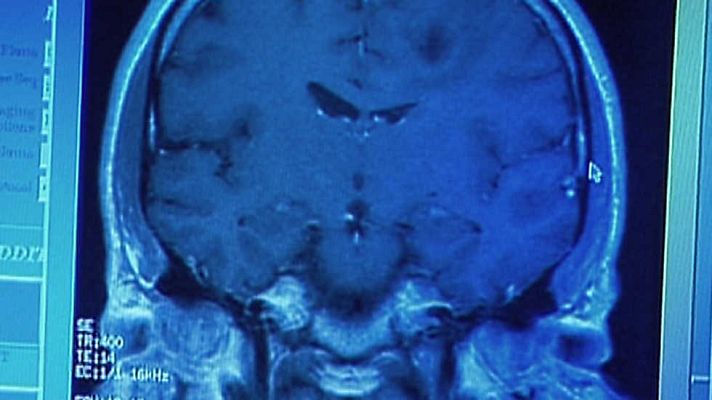

¿Puede medirse el grado de maldad de los seres humanos? Casos mundialmente conocidos como los asesinos en serie o las perversiones cometidas por los soldados de la prisión de Abu Ghraib llevan a investigar qué mueve a las personas a cometer actos tan atroces.

Producción norteamericana que intenta encontrar la fuente de la crueldad humana y plantea, entre otras cuestiones, si el mal es una fuerza espiritual y si puede medirse el grado de maldad de los seres humanos. Este documental realiza un análisis de la maldad humana para buscar las causas más profundas de las que derivan ciertos comportamientos. A través de personas y casos mundialmente conocidos como los asesinos en serie o los soldados de la prisión de Abu Ghraib nos preguntaremos qué lleva a las personas a cometer actos tan atroces.